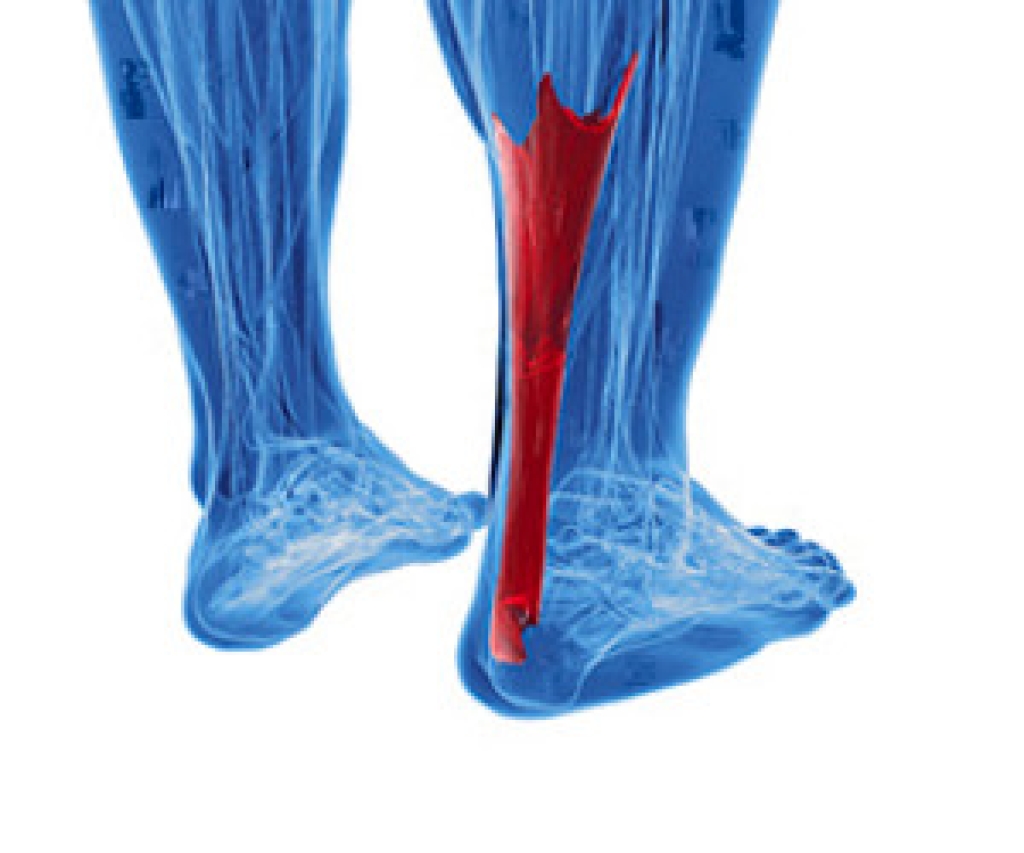

Achilles tendon